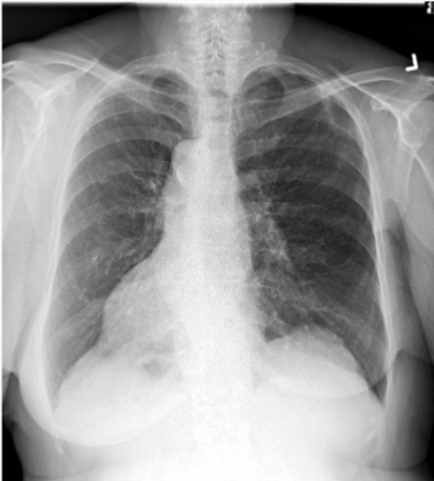

What is this patient presenting with?

Hiatal hernia (note straight fluid line just behind the heart)